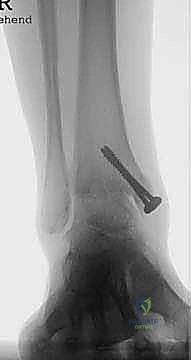

* التصوير الشعاعي المتقدم: صور أشعة سينية (X-rays) في وضعية الوقوف (تحميل الوزن) لتقييم المحور الميكانيكي للساق والقدم.

* الأشعة المقطعية (CT Scan): للحصول على رؤية ثلاثية الأبعاد للعظام، تقييم حجم التكيسات العظمية (إن وجدت)، والتخطيط الدقيق لحجم المكونات المعدنية.

* تقييم التوازن: التأكد من عدم وجود تشوهات في القدم (مثل القدم المسطحة الشديدة أو التقوس) التي قد تؤثر على عمر المفصل الصناعي. إذا وجدت هذه التشوهات، قد يقرر الدكتور هطيف إصلاحها جراحياً في نفس الوقت لضمان بيئة ميكانيكية مثالية للمفصل الجديد.